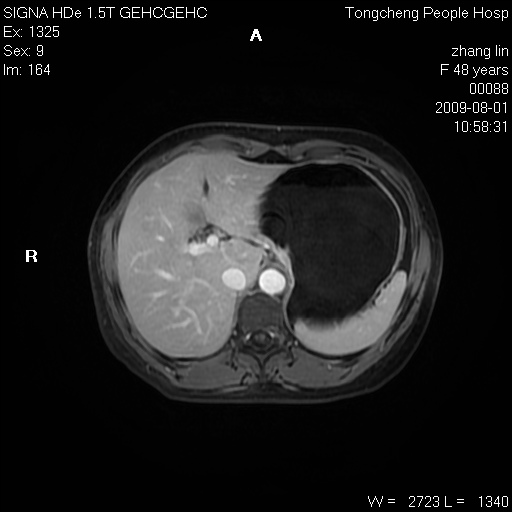

女,48岁。健康体检,彩超发现右肾占位性病变。平素健康。

临床诊断:右肾占位性病变,性质待定(囊肿?肿瘤?)。

上中腹部mr平扫+增强扫描,图像如下:

右肾上极见一类圆形病灶,t1wi呈等信号t2wi呈等高混杂信号,三期增强无强化,边界清---考虑囊肿出血。

慢性胆囊炎